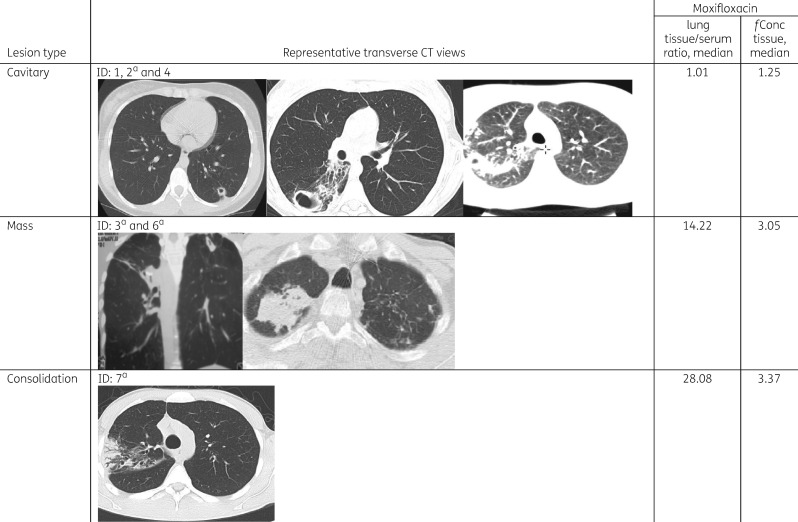

Radiology

Among the seven patients, six had chest CT scans available for review. Cavitary (three) and mass (two) lesions were the dominant abnormalities with the other main lesion identified as a consolidation (one) (Table 3). For the one patient without an available CT for review, the official read of the CT scan in Georgia reported the presence of a cavitary lesion. The lowest free moxifloxacin lung tissue concentrations and tissue/serum ratios were observed in patients with cavitary lesions, followed by mass type lesions and one patient with a consolidation (Figure 2). However, there were no significant differences in the median free moxifloxacin lung tissue concentrations and lung/serum concentration ratios among the four patients with cavitary disease as compared with the two patients with mass lesions.

Figure 2.

Comparison of radiology, moxifloxacin lung tissue/serum concentration ratios and free lung tissue concentration. Among six patients with films available for review three main lesion types were identified including cavitary lesions, mass lesions and one patient with an infiltrate (consolidation). aThe results for subjects 2, 3, 6 and 7 were reported in part in a previous report evaluating the tissue penetration of pyrazinamide.14fConc tissue, free concentration in lung tissue (μg/mL).